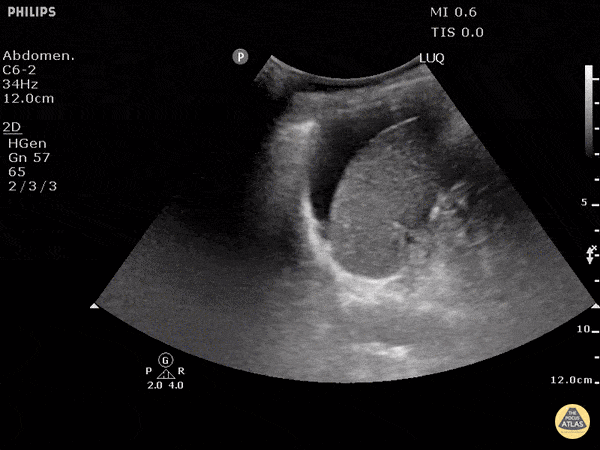

Blunt trauma patient with POSITIVE FAST scan. Free fluid can be seen between the spleen and the diaphragm in this LUQ view. Dr. Justin Bowra